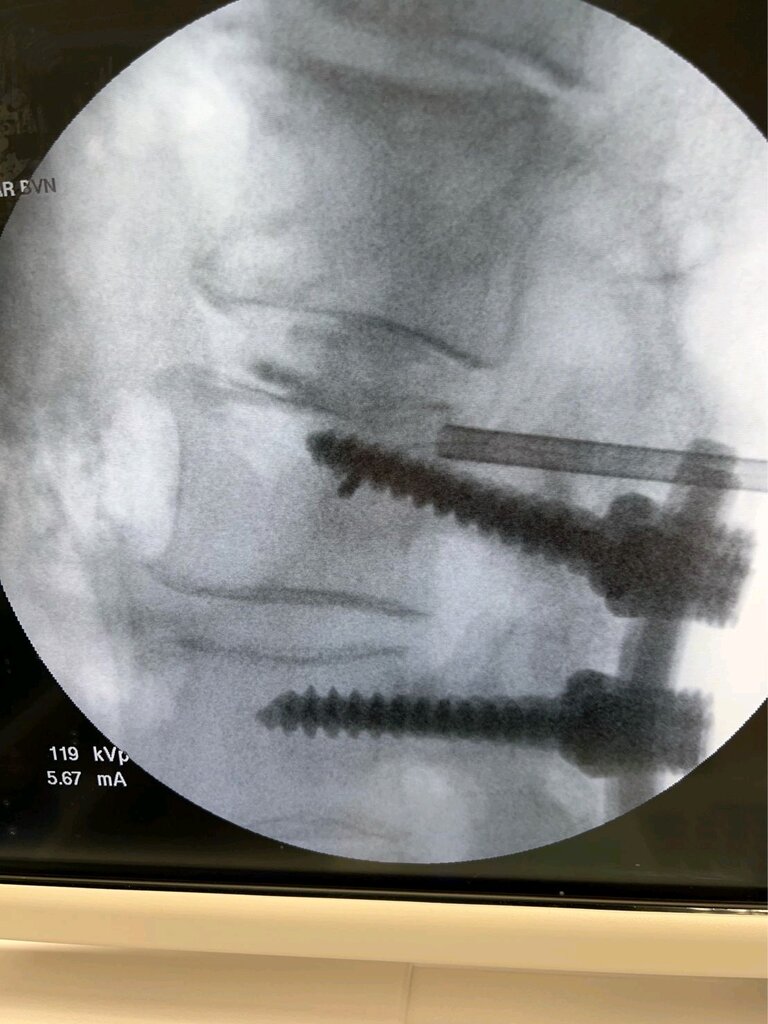

Doug Beall going over the top of screw

Finally did my first one this week. Pretty good anatomy, case went smoothly. 50 minutes, skin to skin. They've gone live with the 7 minute burn protocol, so I'm hoping that the next one I do in a couple of weeks I'll be able to get down to around 35.

Final probe position on these was a little more anterior than I would have liked, but still about 45%, so within range. Next time I'm going to start more laterally to try to aim it closer to the posterior cortex of the body.

Not sure if that AP is your final but looks like it could be obliqued left a few degrees. Can make a huge difference on if you're perfectly midline. Try it next time --get perfect midline placement then oblique a few degrees each way and see how far off midline it can make you, especially if you're more anterior. That skinny part should straddle the SP as well, but I'm assuming you stopped a little short to stay more posterior. Lesion size is pretty big so it's forgiving, just a tip though.

The picture she saved was not the best one. True AP showed ideal placement straddling the spinous process

Can ask your rep to review the “retraction” method with you. Very helpful to get medial without going to anterior when the angle of cannula is not as lateral to medial as ideal, particularly at S1 due to iliac crest. Basically create the usual channel into the cortex of vertebral body with the cannula, Place J stylet, Then slowly rotate to retract the cannula half to 1 cm, coming out of cortex. Then tap in the stylet slowly and the medial curve will start sooner/more dorsal.